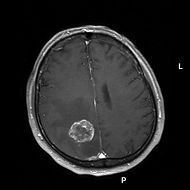

To demonstrate this Dr Shawn Carbonel and colleagues (1) injected breast and skin tumor cells into the bloodstream or fat tissue of mice and then after several days humanely killed the mice determined where in the brain the micrometastases, small colonies of tumor cells that later grow into tumors, were forming, and found that almost all were associated with the blood vessels. There was no sign of any new blood vessel growth, which indicated that the metastases were associating with the blood vessels, and that it wasn’t simply the case that they were promoting the growth of new blood vessels in the vicinity of the growing tumor. To confirm that this is also true in humans they examined tissue samples that been donated following neurosurgery or autopsy and found that almost all metastases were associated with blood vessels, a finding that supported the results of their experiments in mice.

Now they had to answer a new question; were the micrometastases associated with the blood vessels because they have a preference for interacting with the cells of the blood vessel, or simply because the first part of the brain they come to is that adjecent to the blood vessel? To answer this the Oxford scientists injected tumor cells that were labelled with green fluorescent protein directly into an area of the brain allowing equal access to both blood vessels and nerve cells, and using a cranial window in the skulls of the mice were able to observe where the GFP-labelled tumor cells ended up. They observed that the GLF-labelled cells associated almost exclusively with blood vessels, and that the tumors subsequently grow into the surrounding brain tissue.

The tumor cells bind to a blood vessel structure called the vascular basement membrane (VBM), but what the Oxford scientists really wanted to know was what caused the tumor cells to bind to the VBM. Once again using mice with cranial windows fitted they found that an enzyme named focal adhesion kinase was highly active where the tumor cells were interacting with the VBM. Focal adhesion kinase is part of a pathway through which a class of proteins known as the integrins control the interaction between many cells and either other cells or extracellular proteins such as the components of the vascular basement membrane, an observation which suggested that an integrin plays a key role in the binding of tumor cells to the VBM. They next found that a particular integren named Beta 1 integrin is present on all the tumor cell lines they were studying, and that antibodies blocking it could prevent the tumor cells from binding components of the VBM in vitro and to blood vessels in human brain tissue slices.

But would the anti-Beta 1 integrin blocking antibody prevent tumor metastasis in living animals? The answer was yes, the antibodies greatly reduced the growth tumors from human breast tumor cells that were injected directly into the brains of mice. To further emphasize the importance of Beta 1 integrin in brain metastasis they found that when mouse lymphoma cells that had been genetically engineered to lack Beta 1 integrin were injected into mouse brains they formed far smaller tumors than non-GM lymphoma cells.